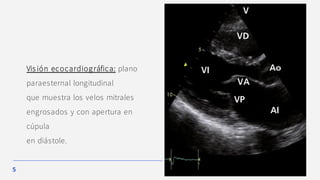

Visión ecocardiográfica: plano

paraesternal longitudinal

que muestra los velos mitrales

engrosados y con apertura en

cúpula

en diástole.

• Los velos valvulares están engrosados y existe una típica apertura valvular en cúpula.

• La aurícula izquierda suele estar agrandada.

La técnica Doppler permite calcular el área valvular.

Si existe insuficiencia tricuspídea secundaria, también permite evaluar la gravedad

Ecocardiograma

Constituye el método incruento más sensible y específico de

diagnóstico.

Además de confirmar el diagnós tico y la gravedad de la estenos is mitral, es útil

para valorar la anatomía y calcificación tanto valvular como subvalvular.

Estos datos son de gran utilidad para valorar la

indicación de valvuloplas tia mitral.